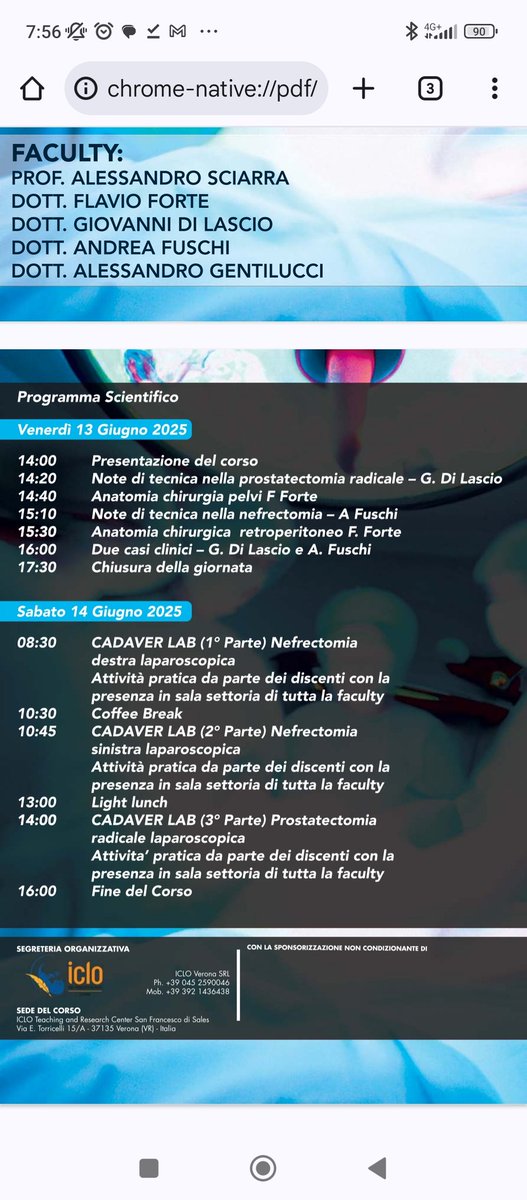

New Edition Verona 13-14 June 2025 Cadaverlab Hands On in Laparoscopic Urological Surgery for the School of Residency in Urology, Sapienza University of Rome. Surgical procedures for radical nephrectomy and radical prostatectomy trainees. Sapienza Policlinico Umberto I European Association of Urology (EAU)

5th Cadaverlab hands on Laparoscopic surgery SAPIENZA UNIVERSITÀ Urologic Residency School ROME. Procedures performed by Residents III IV year: radical nefrectomy - radical prostatectomy. Focus on surgical anatomy and Laparoscopic steps in Major surgery. Sapienza Università di Roma